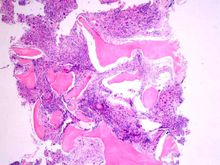

(2)骨髓象:顯示增生明顯活躍,淋巴系占優勢,成熟小淋巴細胞占50%~90%,偶見原始和幼稚淋巴細胞,晚期可見紅、粒、巨三系細胞明顯減少。有溶血時,紅系細胞可見代償性增生。

(3)淋巴瘤:淋巴結呈進行性的無痛性腫大,深部淋巴結腫大可壓迫鄰近器官,血象無特殊變化,骨髓塗片和活檢找到Reed—sternbery細胞或淋巴瘤細胞。淋巴結活檢可見:正常濾泡性結構為大量異常淋巴細胞或組織細胞所破壞;被膜周圍組織同樣有異常淋巴細胞或組織細胞浸潤;被膜及被膜下竇也被破壞。